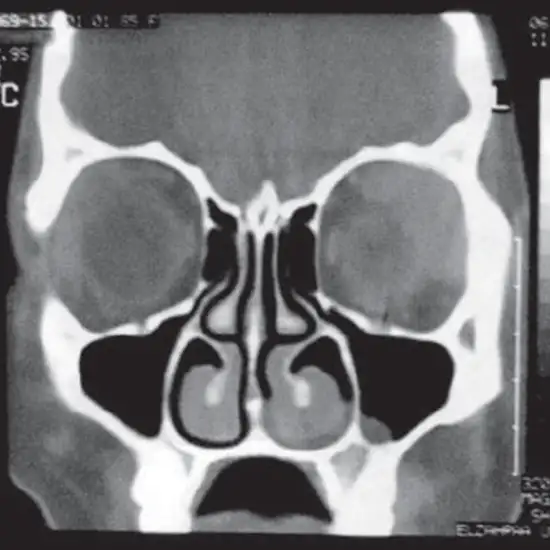

Procedure of CT PNS (paranasal sinus)

CT of the PNS is primarily used to: aid in the diagnosis of sinusitis.

Examine sinuses that have fluid in them or thickened sinus membranes.

detect the presence of infectious diseases

provide additional information on nasal cavity and sinus tumours

By defining anatomy, you can plan for surgery.